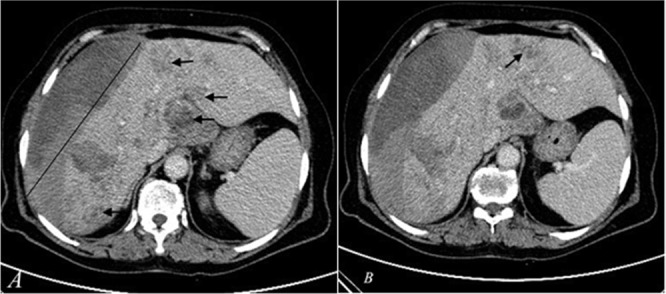

出血是一种非常罕见的法氏囊属(F. hepatica 或 F. gigantica)感染并发症。我们在此报告了土耳其东南部迪亚巴克尔省的三例由肝期法氏囊属感染引起的肝囊下出血病例,其中两例为女性,年龄分别为22岁、66岁和84岁。他们的症状包括右上腹疼痛(3 例)、恶心(1 例)和呕吐(2 例),持续时间从 6 小时到 15 天不等。所有患者的临床表现从中度腹痛到低血容量性休克和缺血性肝炎,均在支持性治疗后得到改善,无需手术。他们在服用曲克芦苯咪唑后,临床和化验指标均完全恢复。总之,肝病出血的病因应考虑法氏囊属感染。

Bleeding is a very rare complication of Fasciola species (F. hepatica or F. gigantica) infection. We present here three cases of subcapsular liver bleeding caused by the hepatic phase of Fasciola spp. infection in patients, two of whom were women, aged 22, 66, and 84 years in Diyarbakir Province, southeastern Turkey. They had symptoms of right upper quadrant pain (n = 3), nausea (n = 1), and vomiting (n = 2) for periods ranging from 6 hours to 15 days. All patients with clinical presentations ranging from moderate abdominal pain to hypovolemic shock and ischemic hepatitis were improved with supportive treatment without the need for surgery. They showed complete clinical and laboratory recovery after triclabendazole administration in their follow-up. In conclusion, Fasciola spp. infection should be considered in the etiology of bleeding from liver disease.